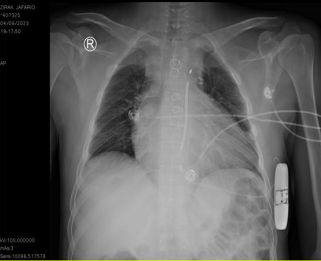

Due to low LVEF and episodes of WCT S-ICD  was implanted(fig 4).

Fig. 4: CXR showed Position of S-ICD after implantation.